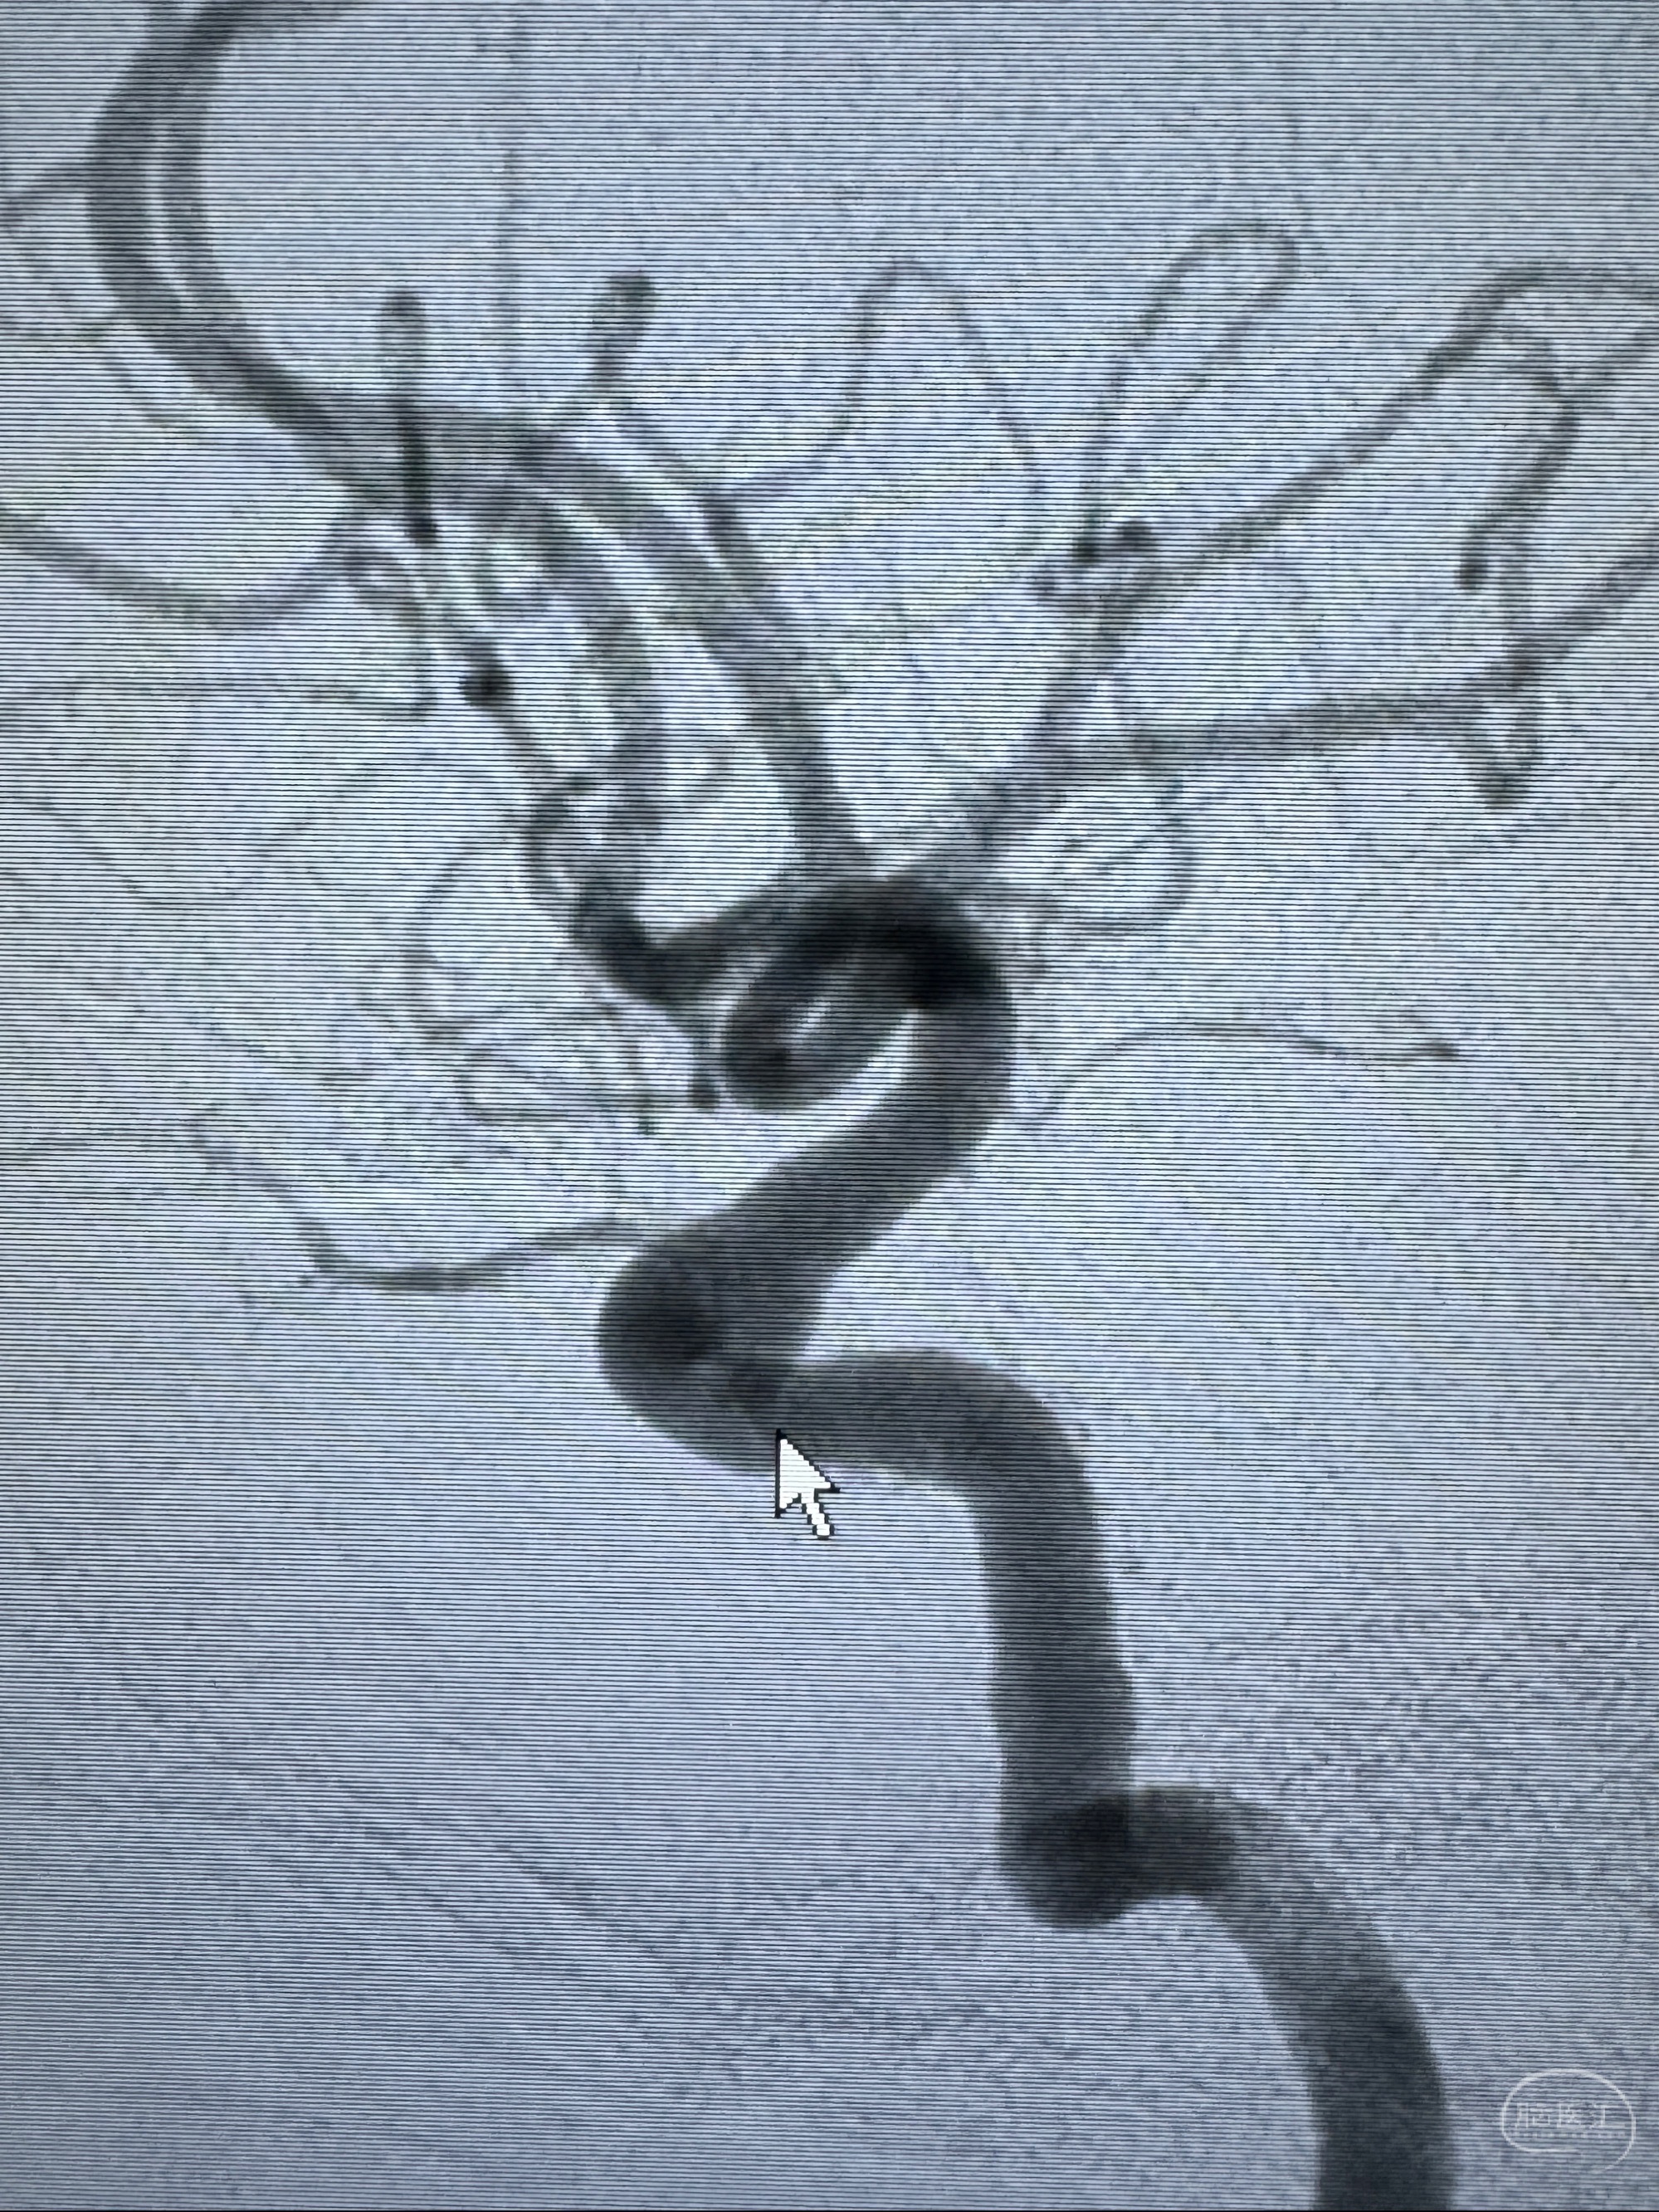

2023-11-13DSA:左侧颈内动脉眼动脉后壁动脉瘤

2023-11-29全麻下行NeuroformEZ4.5-20mm支架辅助栓塞